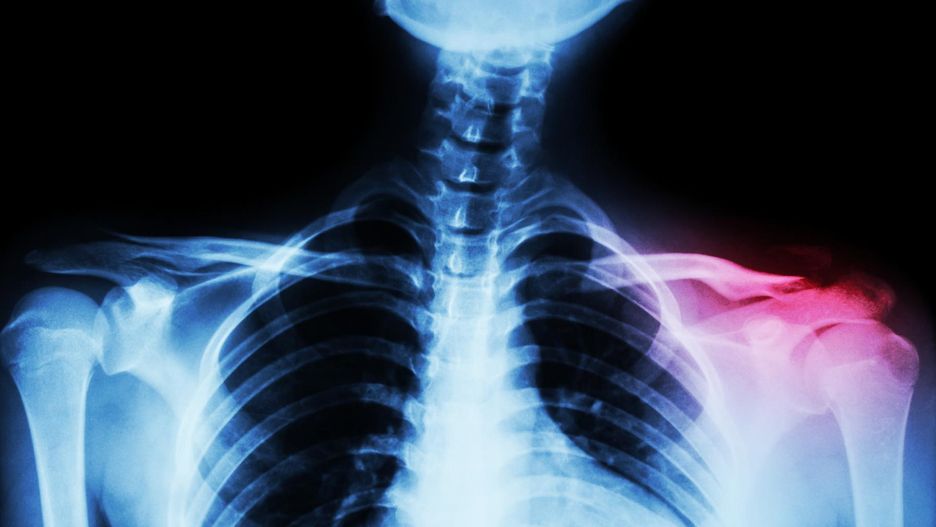

Zwichnięcie stawu barkowo-obojczykowego

Zazwyczaj dokładne badanie lekarskie wystarcza do oceny stopnia uszkodzenia. Niewielka niestabilność świadczy o uszkodzeniu więzadeł barkowo-obojczykowych. Dla potwierdzenia rozpoznania zawsze warto wykonać zdjęcie rentgenowskie. Nie wykaże nam ono uszkodzonych więzadeł, ale pokaże stopień i kierunek przemieszczenia obojczyka oraz uwidoczni ewentualne złamania kostne.